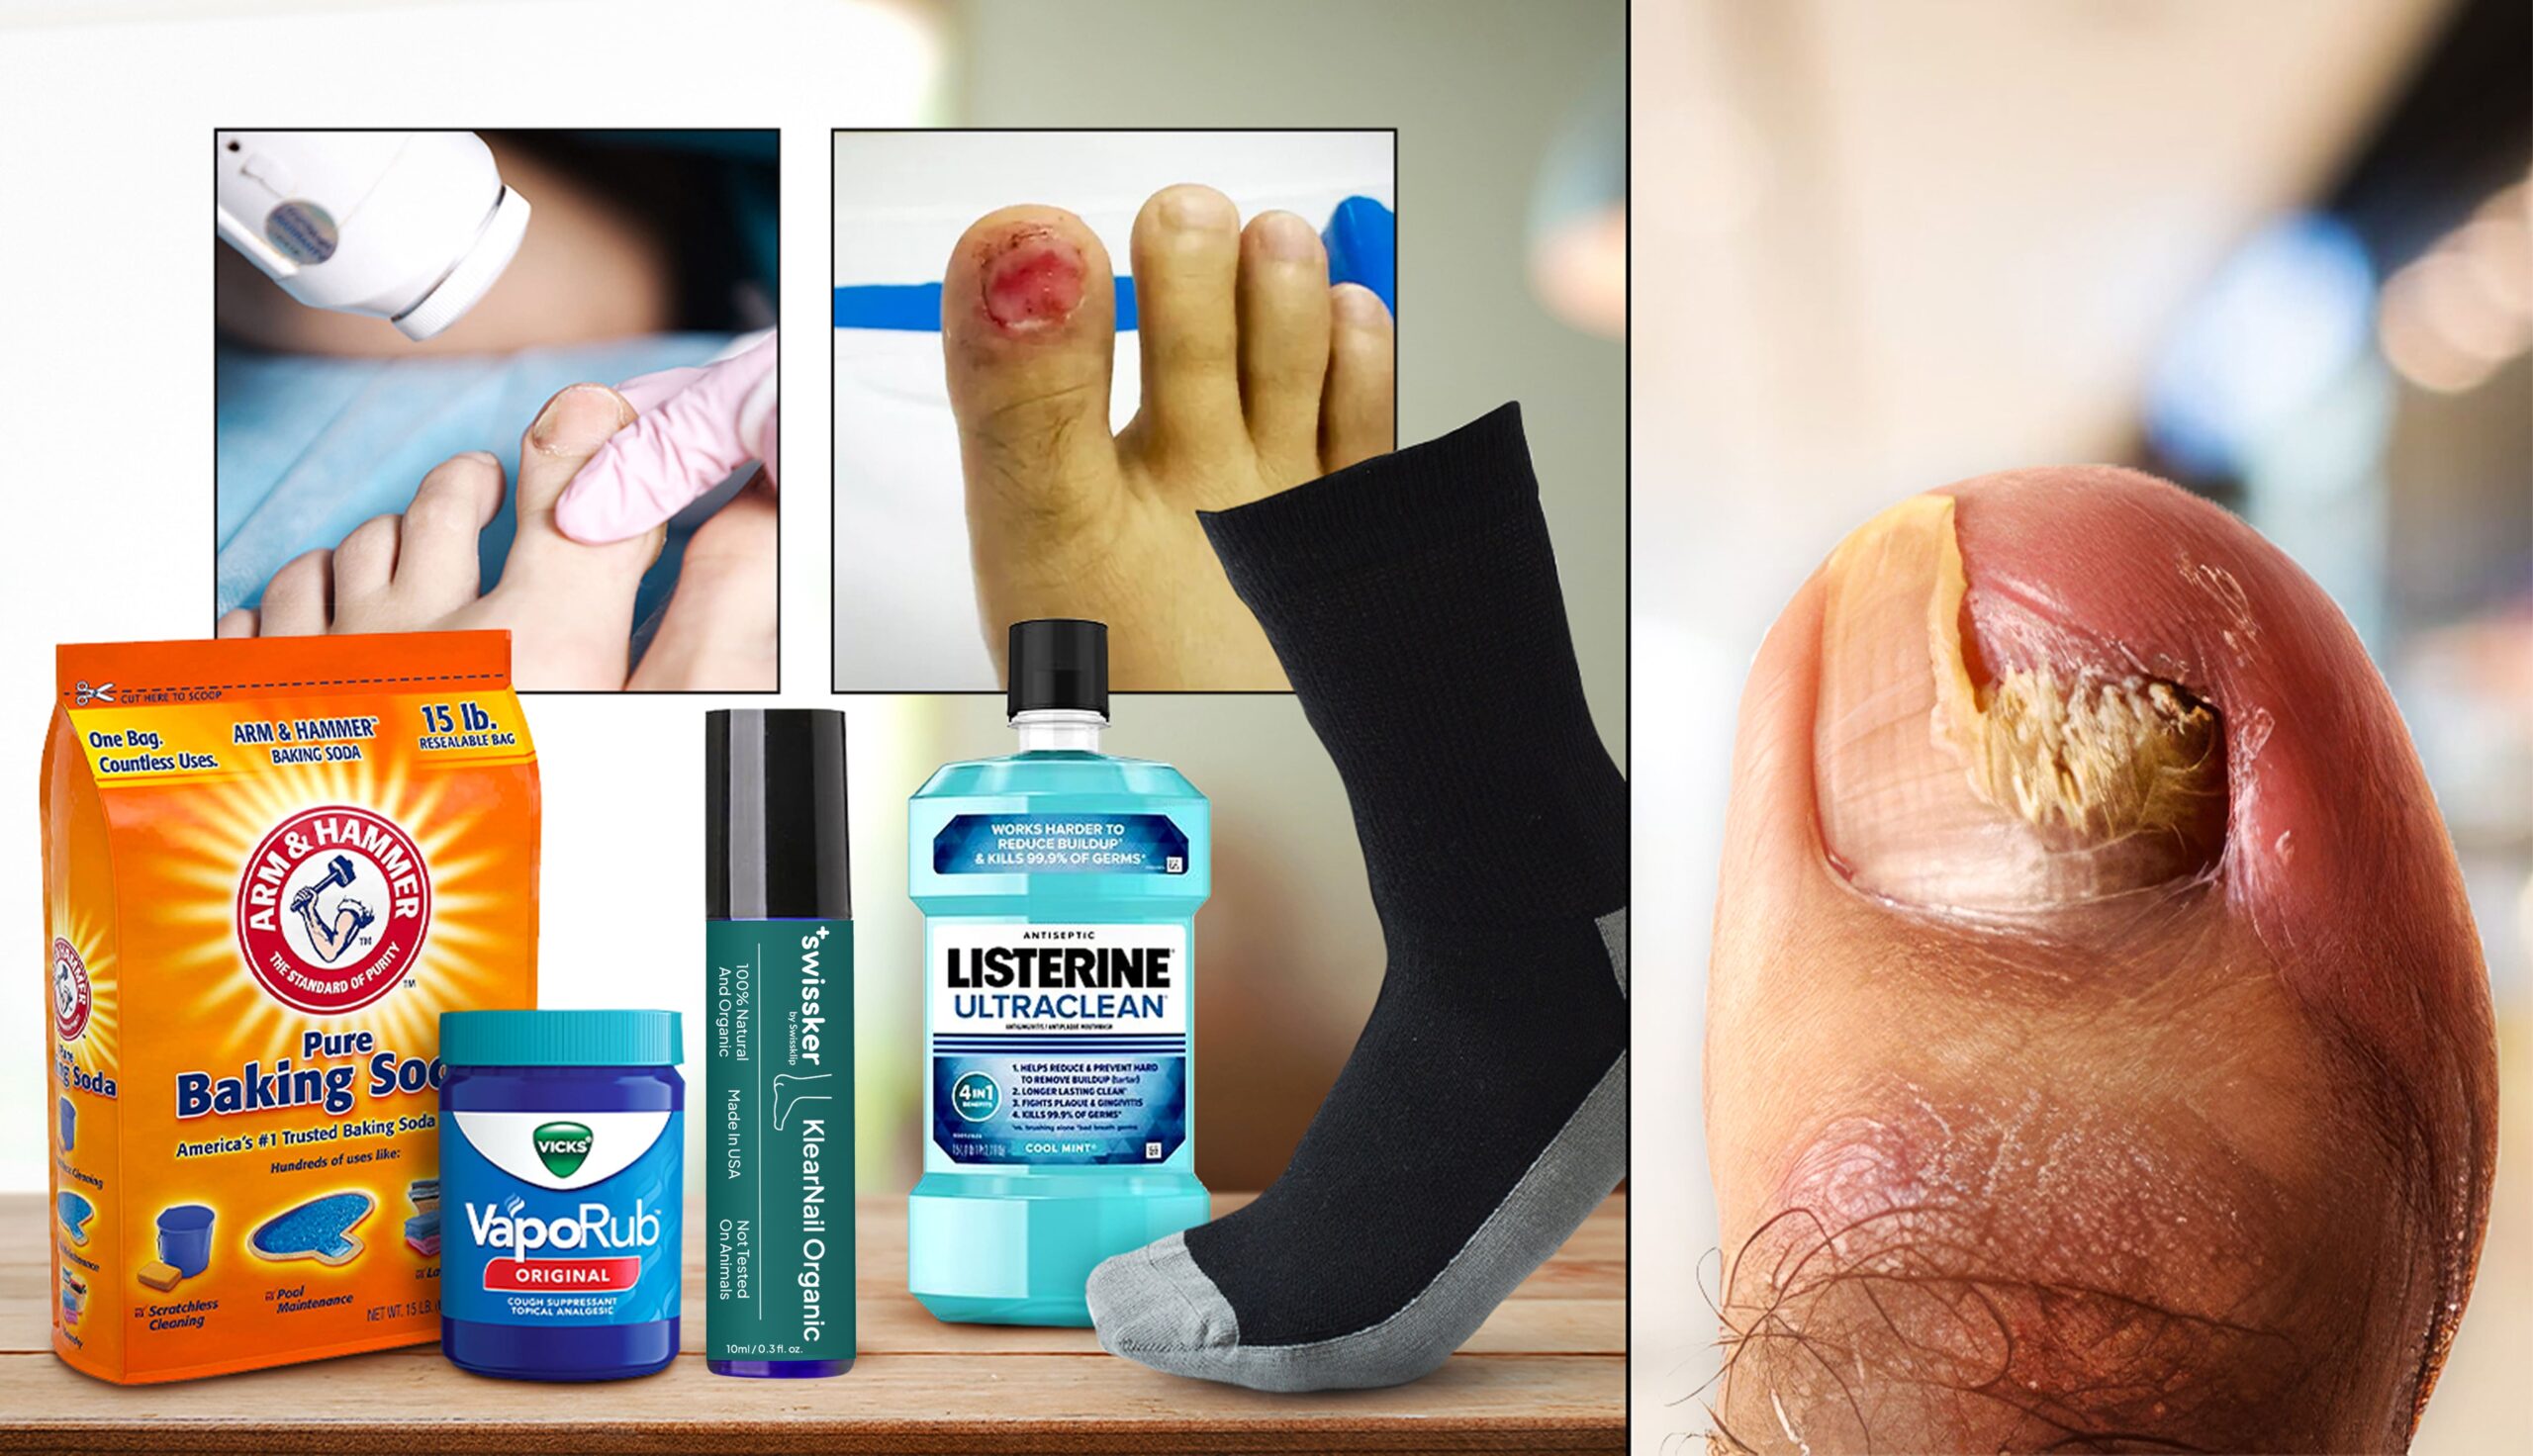

This comprehensive guide evaluates the best methods to eliminate toenail fungus, including professional solutions like laser therapy, advanced at-home treatments such as the Swissklip Anti-Fungal Stick, DIY remedies like baking soda, Vick’s Vaporub, Listerine foot soaks, and Surgical methods like avulsion (nail removal).

Baking soda is a popular DIY remedy for toenail fungus, believed to absorb moisture and inhibit fungal growth. Studies suggest it may prevent fungal growth in up to 79% of cases, but its effectiveness is inconsistent, and scientific support is limited.

Baking soda can be applied as a paste, used in foot soaks, or sprinkled into shoes to reduce moisture. While affordable and natural, it is not as fast-acting or reliable as proven treatments. Results take time and may not fully resolve the issue.

“Patients seeking proven results should consider other options first.” – Dr. Emily Splichal, DPM

Effectiveness: 60%

Safety: 70%

Price: $150-$300 (per procedure)

Overall:2.5/5

Nail removal, or avulsion, is a treatment for severe toenail fungus involving partial or complete removal of the nail. Non-surgical removal uses urea ointment to soften the nail for easy extraction, while surgical removal requires local anesthesia to separate the nail from the bed. Though effective for extreme cases, it’s invasive, costly, and risky, as it can become infected and have an irregular nail regrowth. A new nail may take 12–18 months to grow back, and results aren’t guaranteed.

Nail removal is a last-resort option with significant risks. Doctors recommend that safer, more effective treatments should be considered first.